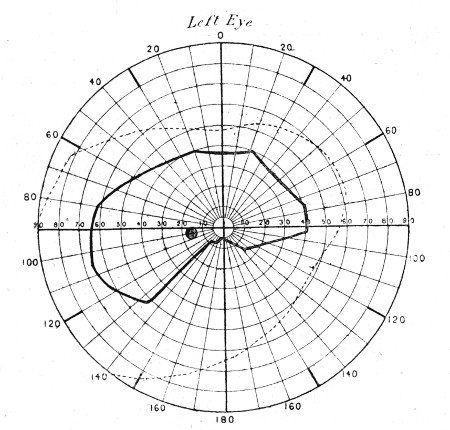

73. Visual Field in Occipital Injury 279

74. " " " 279

75. " " " 281

76. " " " 281

77. " " " 283

78. " " " 283